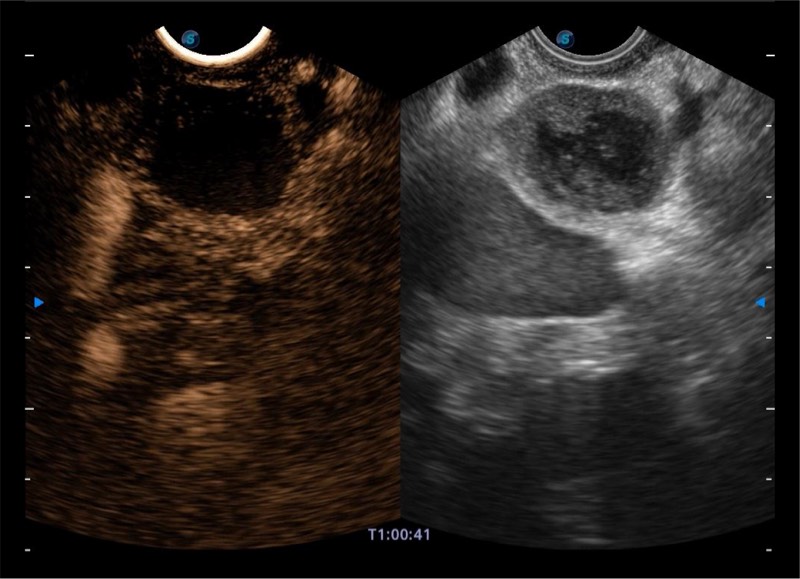

基于二十年的超声技术积累,玖鼎集团提供了最新一代的独立超声主机,在提供高质量图像的同时满足多学科使用。具备常见多普勒技术并提供弹性成像、声学造影等高端影像技术。新一代传感器具有更强的抗干扰能力并减少图像伪影。

• 4-12MHZ宽频输出